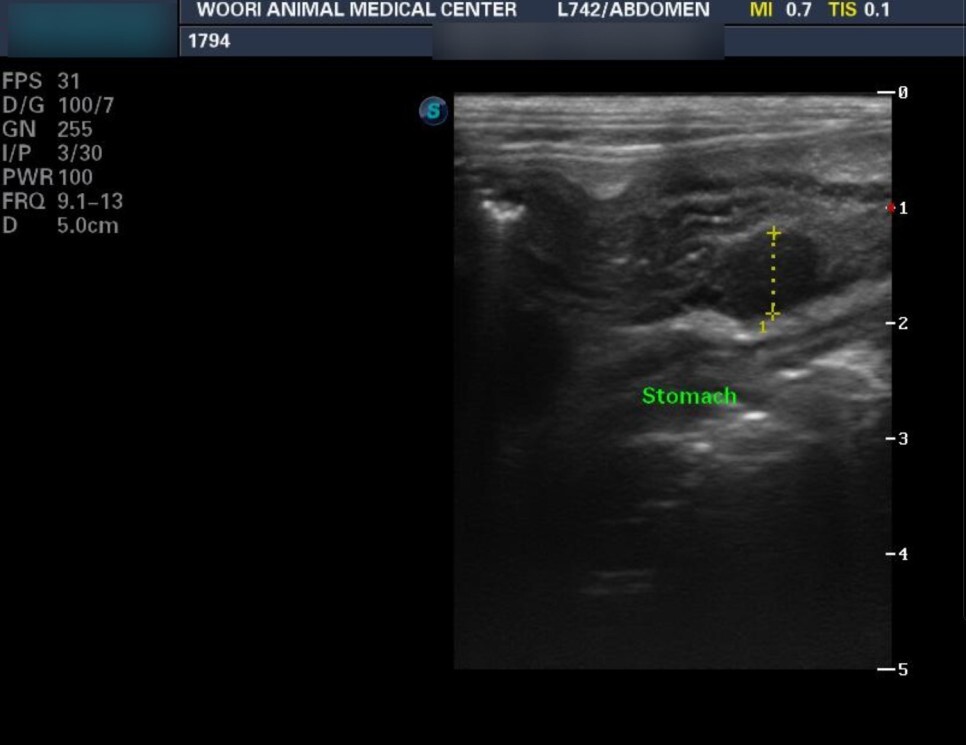

방사선 및 초음파에서는 위벽이 비후 되어

있는 것을 관찰할 수 있었습니다.

조직 검사를 위한 샘플 채취 방법 중 내시경을

통한 방법이 있지만 초음파 검사상 위 점막보다는

벽측(복강쪽)이 비후된 것으로 의심되어 개복술을

진행한 케이스입니다.